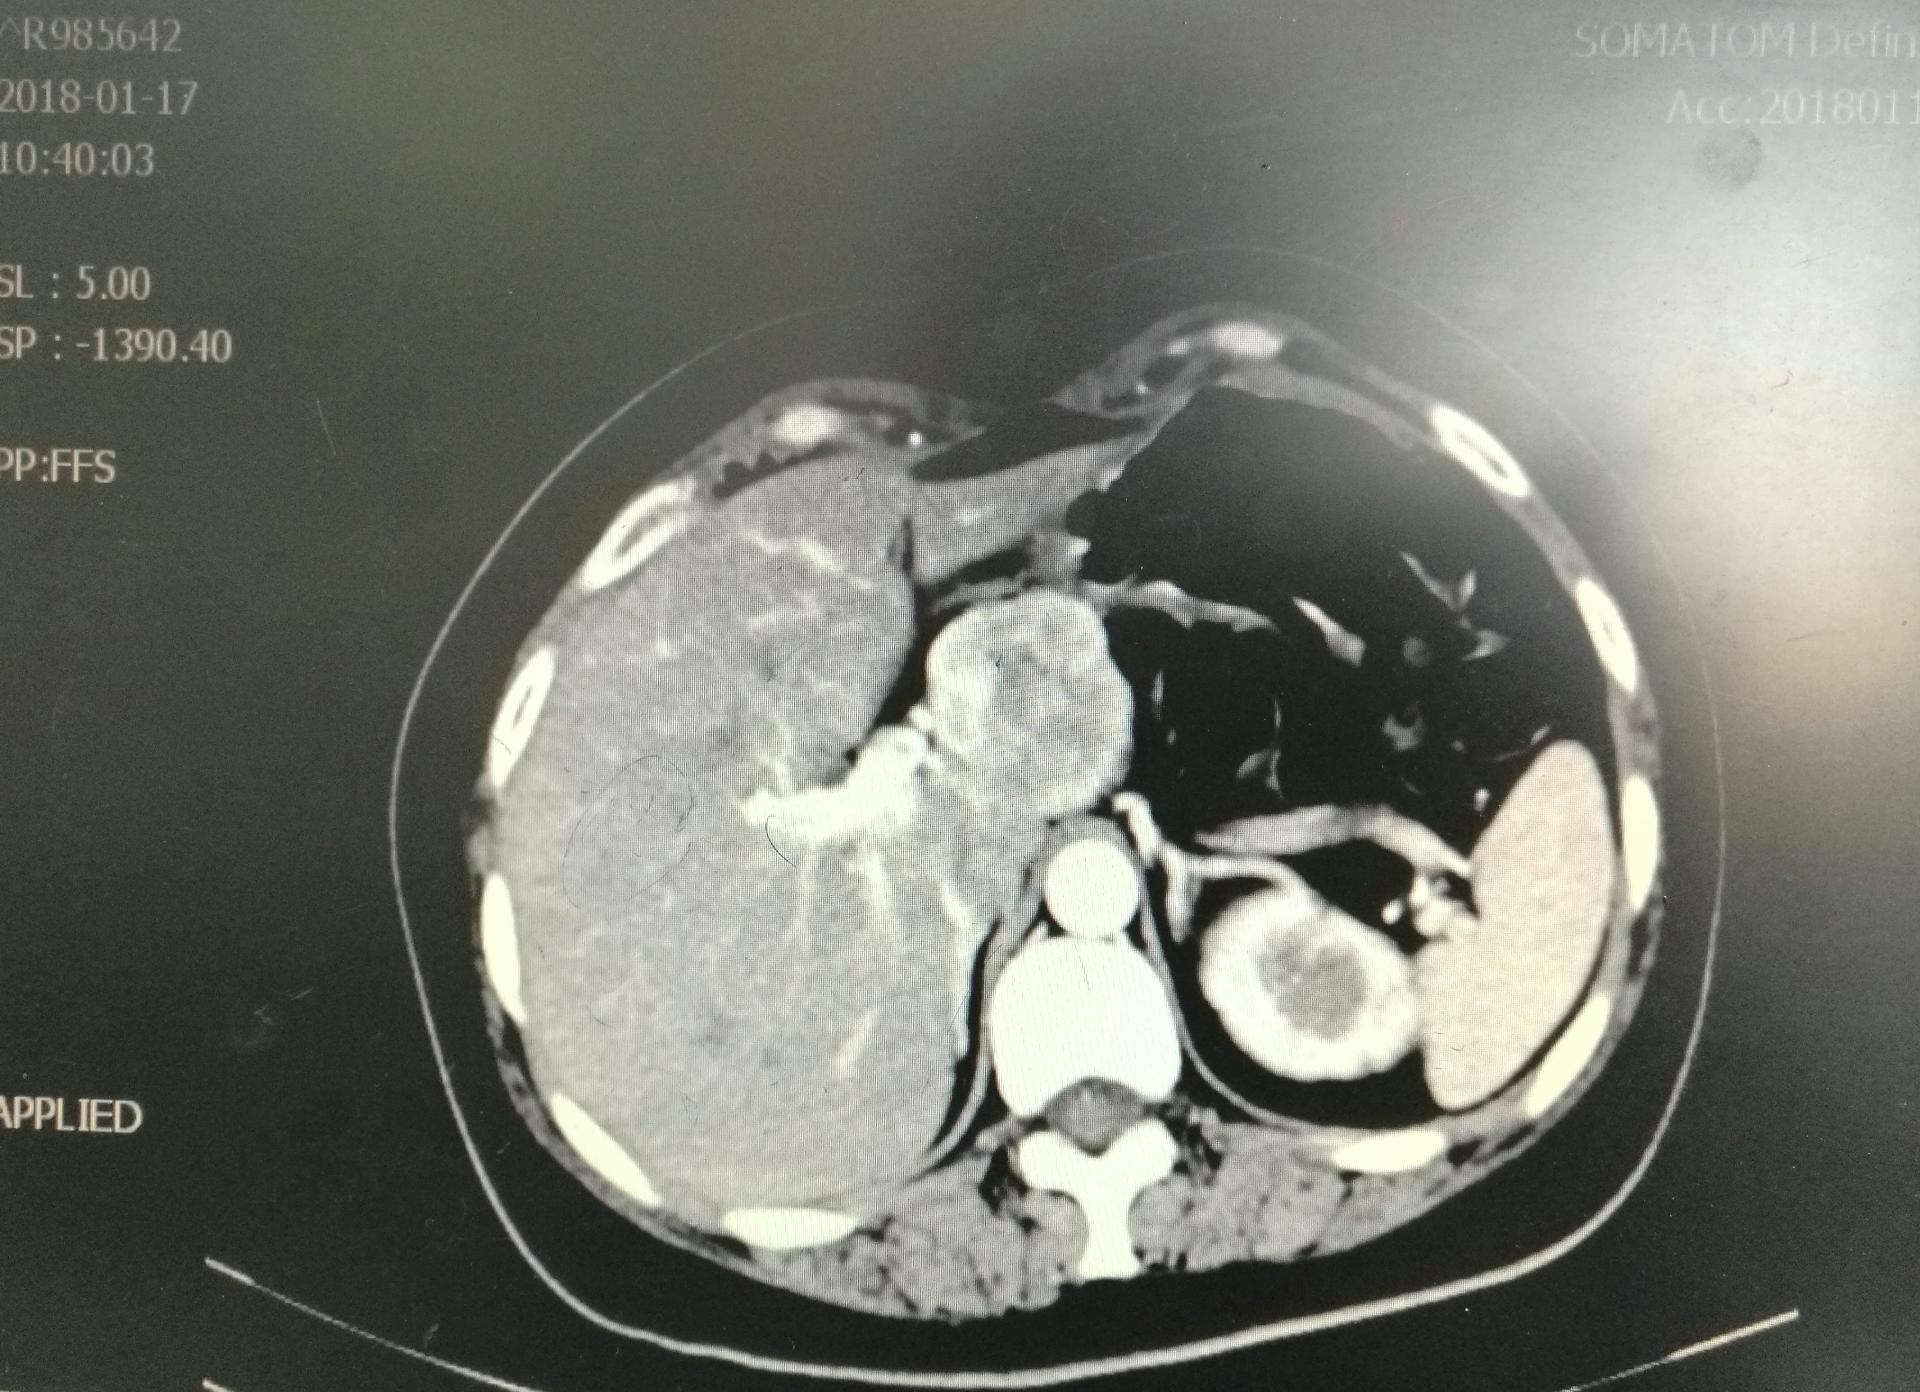

患者王女士有糖尿病史多年,并有剖宫产史。因反复呕吐3月曾多次就诊于市区医院,但呕吐症状无好转,今年1月16日转至中心医院消化介入科住院治疗,主治医师金小军、蒋晓芬接诊后积极予以护胃、止吐及营养支持等治疗,查腹部增强CT、MRI提示肝脏左尾叶肿瘤,血管平滑肌瘤可能,腹白线疝(大网膜疝入),肺部感染。于是启动MDT模式,1月25日转入肝胆胰外科进行术前准备,经过和贺亚东主任医师、CT影像黄崇权副主任,内分泌科余玉慧主任,麻醉科李宇副主任,呼吸科黄阳副主任医师术前多学科讨论,认为患者糖尿病多年,血糖控制不理想,并于不久前曾行异位妊娠人流术,体质虚弱同时存在肺部感染,营养不良,NRS2002>3分。决定先予以营养支持治疗,控制血糖,继续控制肺部感染后,再进行腹腔镜下手术治疗。

根据目前较为通用的Couinaud 肝脏分段分叶方法,肝尾状叶为第一段,位于肝脏背面,位置极深,且周围被大血管包裹,王女士的肿瘤正好位于左尾状叶,直径4.5公分,位置非常特殊,上接左肝内叶,下连人体最大的静脉血管-下腔静脉,手术中容易损伤导致大出血、气体栓塞而导致手术失败,因此这里一直是肝脏外科手术的禁区,曾被黄志强院士称为“肝脏外科的最后禁区”,令很多外科医生望而止步。需要手术医师胆大心细、对解剖了如指掌,同样需要有在“刀尖上舞蹈”的勇气。在上世纪90年代以后,该手术才开始在国外陆续开展,国内也只有个别大的肝胆外科中心能够实施该高难手术,腹腔镜下肿瘤切除难度更高。